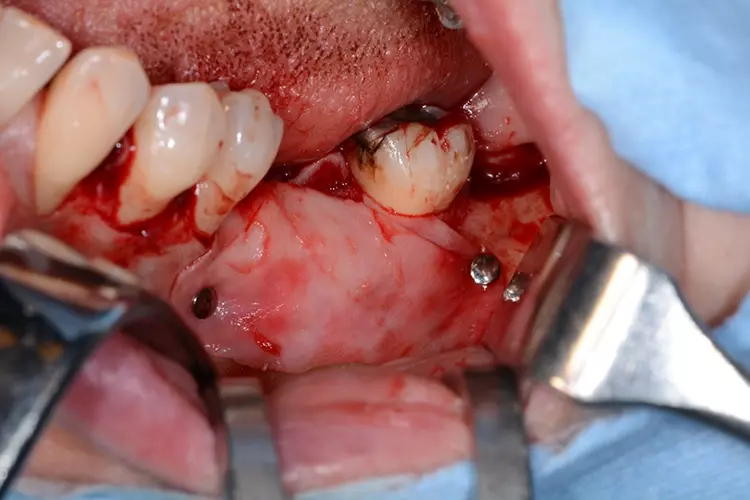

Der Wundrand wurde mit monofilem, nicht resorbierbarem Nahtmaterial in Kombination aus Rückstich- und Einzelknopfnähten vernäht (Abb. 10). Die postoperative Röntgenaufnahme zeigt im Bereich der horizontalen Augmentation eine suffiziente knöcherne Regeneration (Abb. 11).

Im vorliegenden Patientenfall wurde eine resorbierbare Biomembran aus Kollagen ausgewählt. Neben einer Bioresorbierbarkeit und einer geringen Immunogenität bieten resorbierbare Membrane den Vorteil, dass nach Einheilung des Augmentats kein zusätzlicher chirurgischer Eingriff für die Materialentfernung anfällt [2]. Bei Einsatz von nicht-resorbierbaren Pins oder Osteosyntheseschrauben zur Membranfixierung ist allerdings ein zweiter chirurgischer Eingriff zur Materialentfernung notwendig.

In Bezug auf die Fixierung versus Nicht-Fixierung der Membran werden unterschiedliche Meinungen diskutiert. Einige Autoren behaupten, dass durch die Membranfixierung die Volumenstabilität der Membran sowie der Knochenaugmentation und damit ein höherer Erfolg der GBR erreicht werden kann [14,15]. Demgegenüber wird behauptet, dass trotz Fixierung der Membran, durch den Wundverschluss und während der Einheilphase unerwünschte Migrationseffekte der Membran und der Knochenaugmentation nicht vermieden werden können [16].